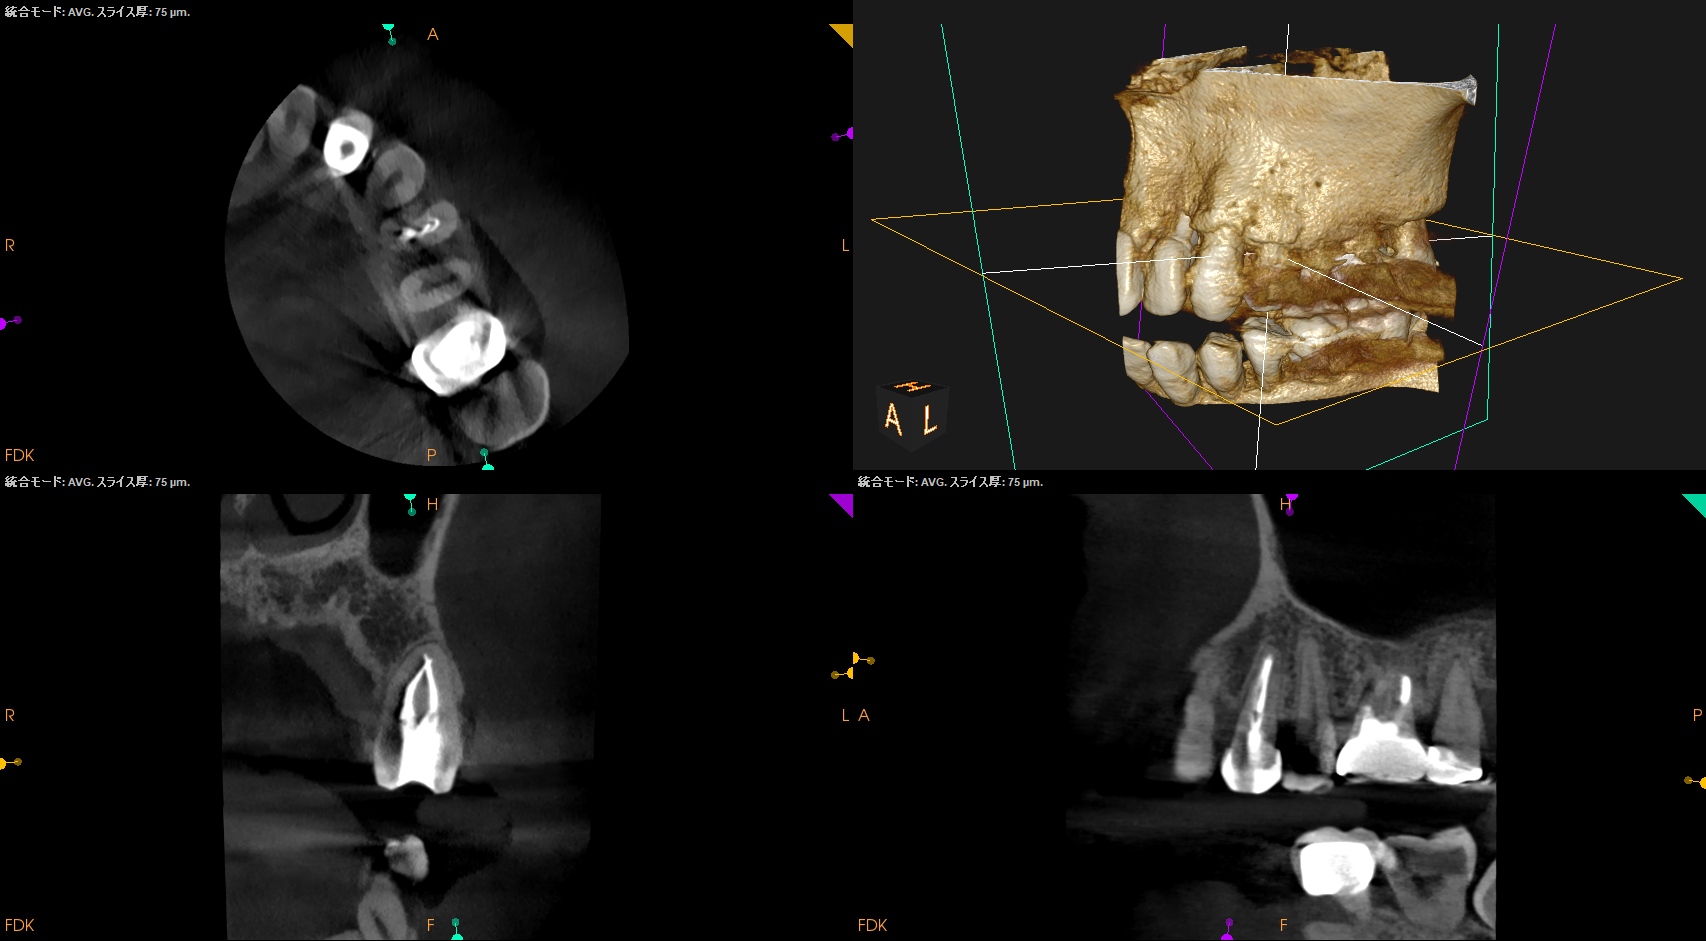

#12 RCT(2026.1.6)

露髄させると…

暗赤色の出血である。

が、Cold testには反応していないのに、だ。

歯髄の病態は奥が深いと言えるだろう。

と同時に、もうなんと言おうと成人での歯髄に近接する歯内療法処置はトラブルを生むことがここでもよくわかるだろう。

また、治療前のCBCTで2根管性のことから合流部位の確認をいつものように行った。

問題はないだろう。